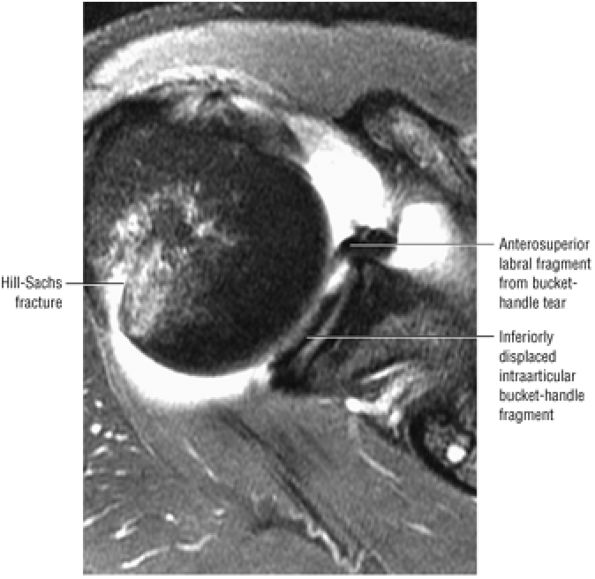

FIGURE 8.102 ● (A) The anterior undersurface of the acromion and the coracoacromial ligament form the coracoacromial arch. The subacromial subdeltoid bursa facilitates the passage of the rotator cuff and proximal humerus under the coracoacromial arch. (B) A superior axial image shows the anterior-to-posterior extent of the coracoacromial (CA) ligament perpendicular to the supraspinatus tendon. The fluid in the subacromial-subdeltoid bursa represents fluid between two serosal surfaces in contact with each other. One serosal surface is contributed by the undersurface of the coracoacromial arch and deltoid, and the other serosal surface is on the bursal side of the cuff.

|

![]() |

FIGURE 8.103 ● Pseudospur. The normal broad attachment of the coracoacromial ligament to the inferior surface of the acromion is shown on (A) T1-weighted coronal oblique and (B) sagittal oblique images. The low-signal-intensity acromial cortex (black arrows) and adjacent coracoacromial ligament and lateral slip of the deltoid attachment (white arrows) give the false impression of a small subacromial spur in the coronal plane. This pseudospur should not be misinterpreted as impingement; otherwise, unnecessary acromioplasties may be performed on patients with a normal coracoacromial ligament attachment and no associated acromial spurs.